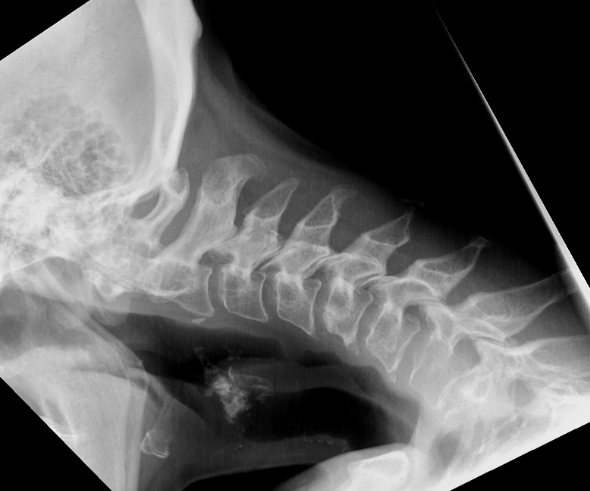

首のレントゲンでは「まっすぐ前を向けているか」を確かめ、(可能であれば)うつ伏せでの撮影も行って首の動きや姿勢の変化を見ます。全身のバランスを見るために、背骨全体の立位レントゲンも撮り、背中が強く丸くなることで首が下がっていないかを確認することもあります。

首下がりのレントゲン(Copyright:Balgrist University Hospital)